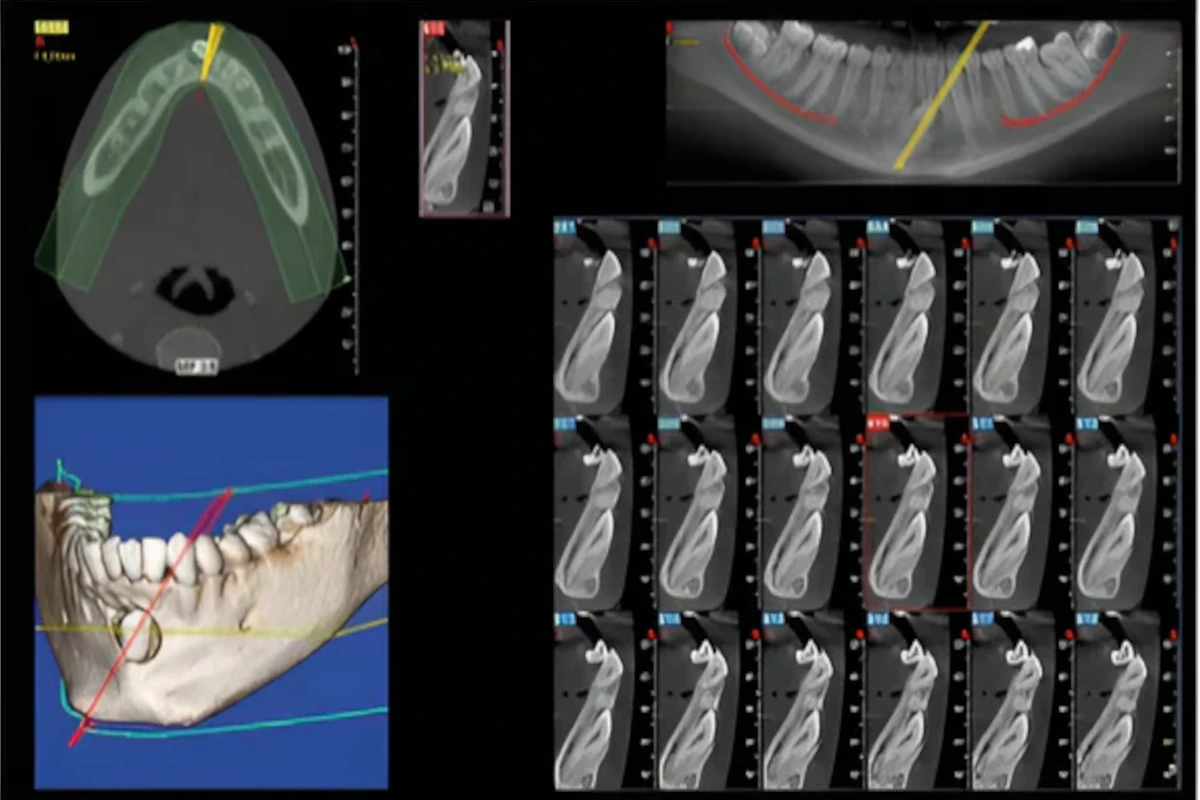

Three-dimensional radiographic imaging is a scientific achievement with many advantages, offering a more accurate and safer diagnostic tool. Today, three-dimensional radiographic imaging through Cone Beam Computer Tomography (CBCT) in modern dental practice is a valuable diagnostic tool, particularly in cases of anatomical challenges encountered in implant planning or general dental treatments (e.g., the inferior alveolar nerve, nasal and paranasal sinuses). Proper and accurate planning protects the patient while also providing unique treatment planning protocols and loading strategies for dental implants. The much greater imaging accuracy compared to a traditional Dental CT allows for the digital placement of implants on a computer using data from the radiograph, facilitated by specialized software. This ensures more precise planning and enhances patient safety.

Thus, this machine could be considered a valuable diagnostic and communication tool, as the treatment plan can now be presented tangibly to the patient before execution. This ensures safety, comfort, rapid recovery, and more accurate imaging and planning (immediate loading – same day teeth). The low radiation dose, nearly equivalent to that of a panoramic X-ray machine, combined with the very short exposure time compared to a conventional CT scan, represents a technological advancement primarily aimed at dental patients, as it minimizes their radiation exposure while providing much more accurate imaging capabilities than other devices. The machine can focus radiation solely on the cranial area, specifically the jaws and maxillary sinuses, making it suitable for dental use only. Its potential applications span every dental field, from general to specialized dentistry, wherever detailed jaw imaging is necessary.

Its use is intended both for patients needing dental-type X-rays and for dentists who can utilize it for diagnostic purposes in a limited field, providing more accurate imaging in cases such as endodontics, temporomandibular disorders, or even a simple panoramic X-ray, among others. The application of three-dimensional Cone Beam Computed Tomography (CBCT) is not limited to implantology but extends to every area of dentistry, making it a valuable and essential diagnostic tool today.

A CT scanner designed exclusively for dental use, with applications in implantology, endodontics, orthodontics, periodontology, and oral surgery. Anteroposterior and lateral cephalometric X-rays can be derived from a single initial CT scan, further reducing radiation exposure for the patient, especially when these imaging methods are necessary for young patients undergoing orthodontic treatment. It offers very low radiation exposure, comparable to a simple panoramic X-ray but with three-dimensional imaging. The radiation dose is 20 to 50 times lower than that of conventional CT scans. It also provides a very thin slice thickness, 5 to 15 times smaller than that of a traditional CT scan, where indicated (digital treatment planning – guided surgery).

The ability to digitally read and modify volumetric data in the dental office by the referring dentist allows for precise 1:1 measurements, focusing on either the upper or lower jaw depending on the occlusal plane, or even a single tooth without the distortion present in panoramic X-rays. It offers a very small focal spot and high resolution. The field of view is larger compared to a panoramic X-ray (6-12 inches). The imaging is simple, safe, accurate, fast, and provides more detailed three-dimensional images. The actual exposure time is minimal since the radiation is pulsed and adjusted based on the patient's size (40% less radiation for children than adults). Multiple 360-degree images are captured with a single simple rotation using cone-beam radiation, whereas in traditional CT scans, the patient is typically irradiated transversely with multiple rotations. The digital design of the treatment plan serves as a communication tool between the dentist and the patient.